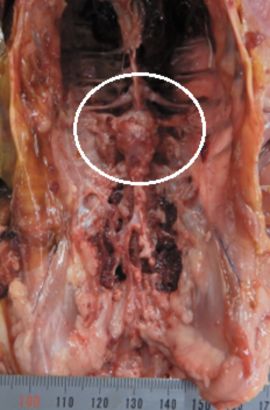

上の写真では、第6胸椎の周辺(白い円の内部)が膨隆していることが分かります。膨隆部内腔は、黄色の膿が確認されました。弊社で、この膨隆部から菌分離を実施した結果、ECが分離されました。